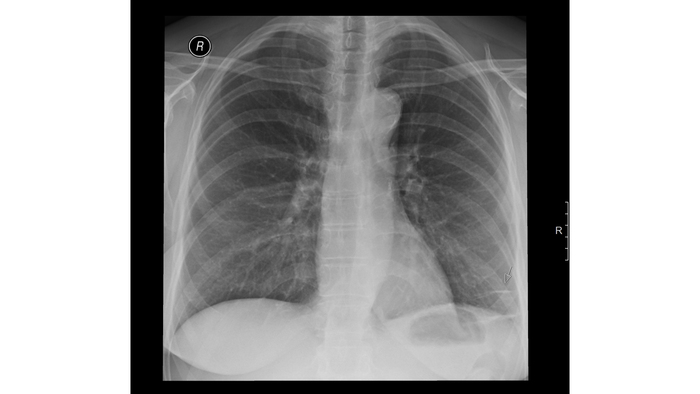

Расшифровка цифровых кодов флюорографии с примерами

19 - Изменения диафрагмы, не связанные с плевральной патологией (диафрагмальная грыжа, высокое стояние диафрагмы и т. д.).